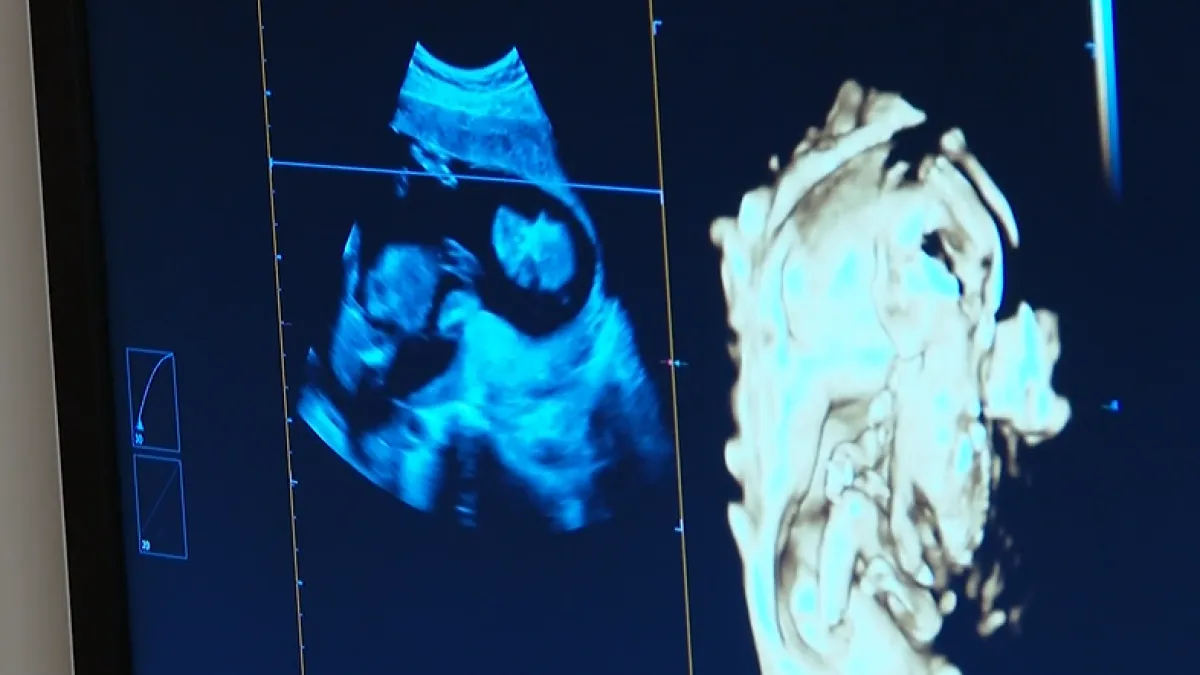

Milijun potpisa, žestoka svađa i glasanje koje trese EU: Pravo na pobačaj ili kultura smrti?